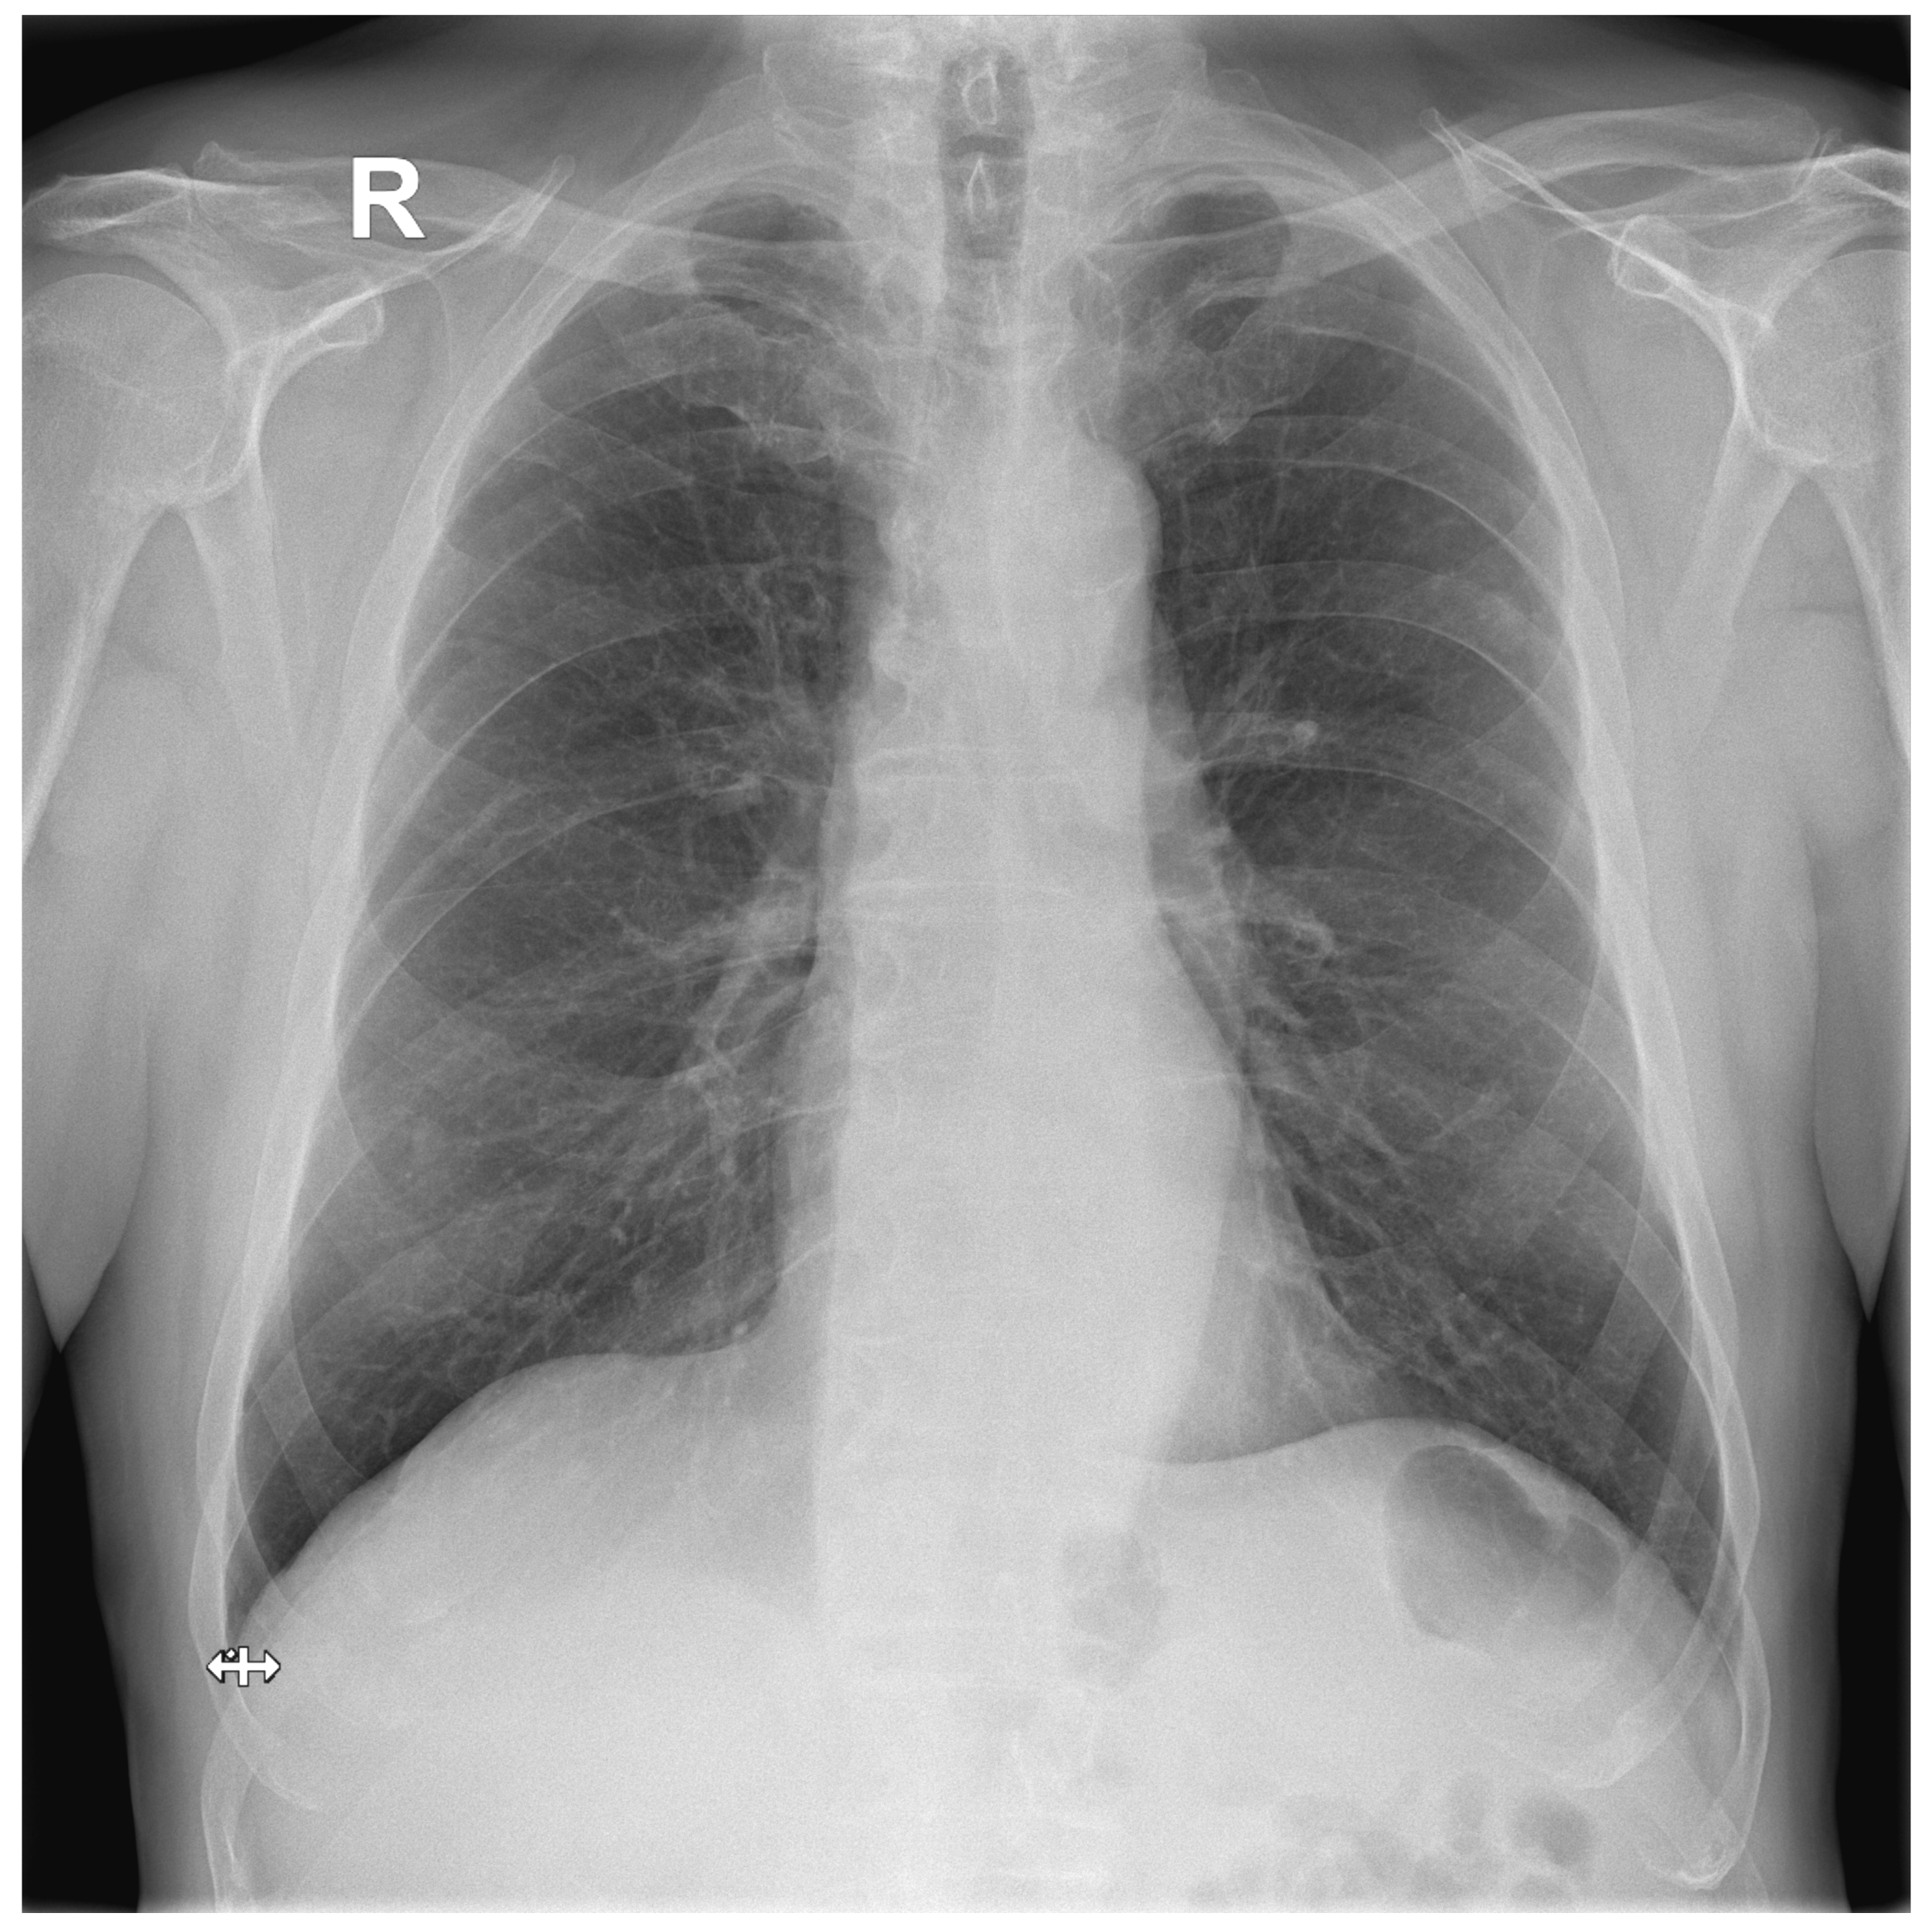

Figure A2.

False Negative image #1 incorrectly classified by DLAD software during the retrospective study. The software failed to detect a lesion in lung parenchyma. Assessed radiologists #5f0 and #24a also incorrectly classified this image as Normal.